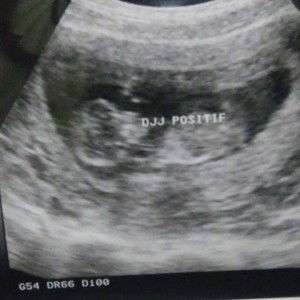

Selamat pagi bunda, mau tanya nih Di sini ad gak yang udh hamil 4 bulan tapi perut nya gak kelihatan buncit?? Saya sudah hamil 4 bulan tapi perut saya gak keliatan buncit, saya tkut dan kefikiran kalau di bilang orng hamil udh 4 bulan perut gak gede ? Tpi hasil USG alhamdulilah normal semua janin sya ??